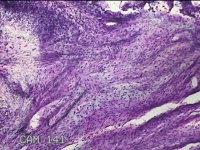

宫颈锥切物

女

31岁

宫颈上皮内瘤变

妇检发现宫颈CIN2 2个月。

灰白暗红色组织2.8x1.8x0.3cm一块,表面糜烂,切面灰白暗红色,质软。

所提供图片不具有诊断价值。

为什么不拍鳞状上皮呢?